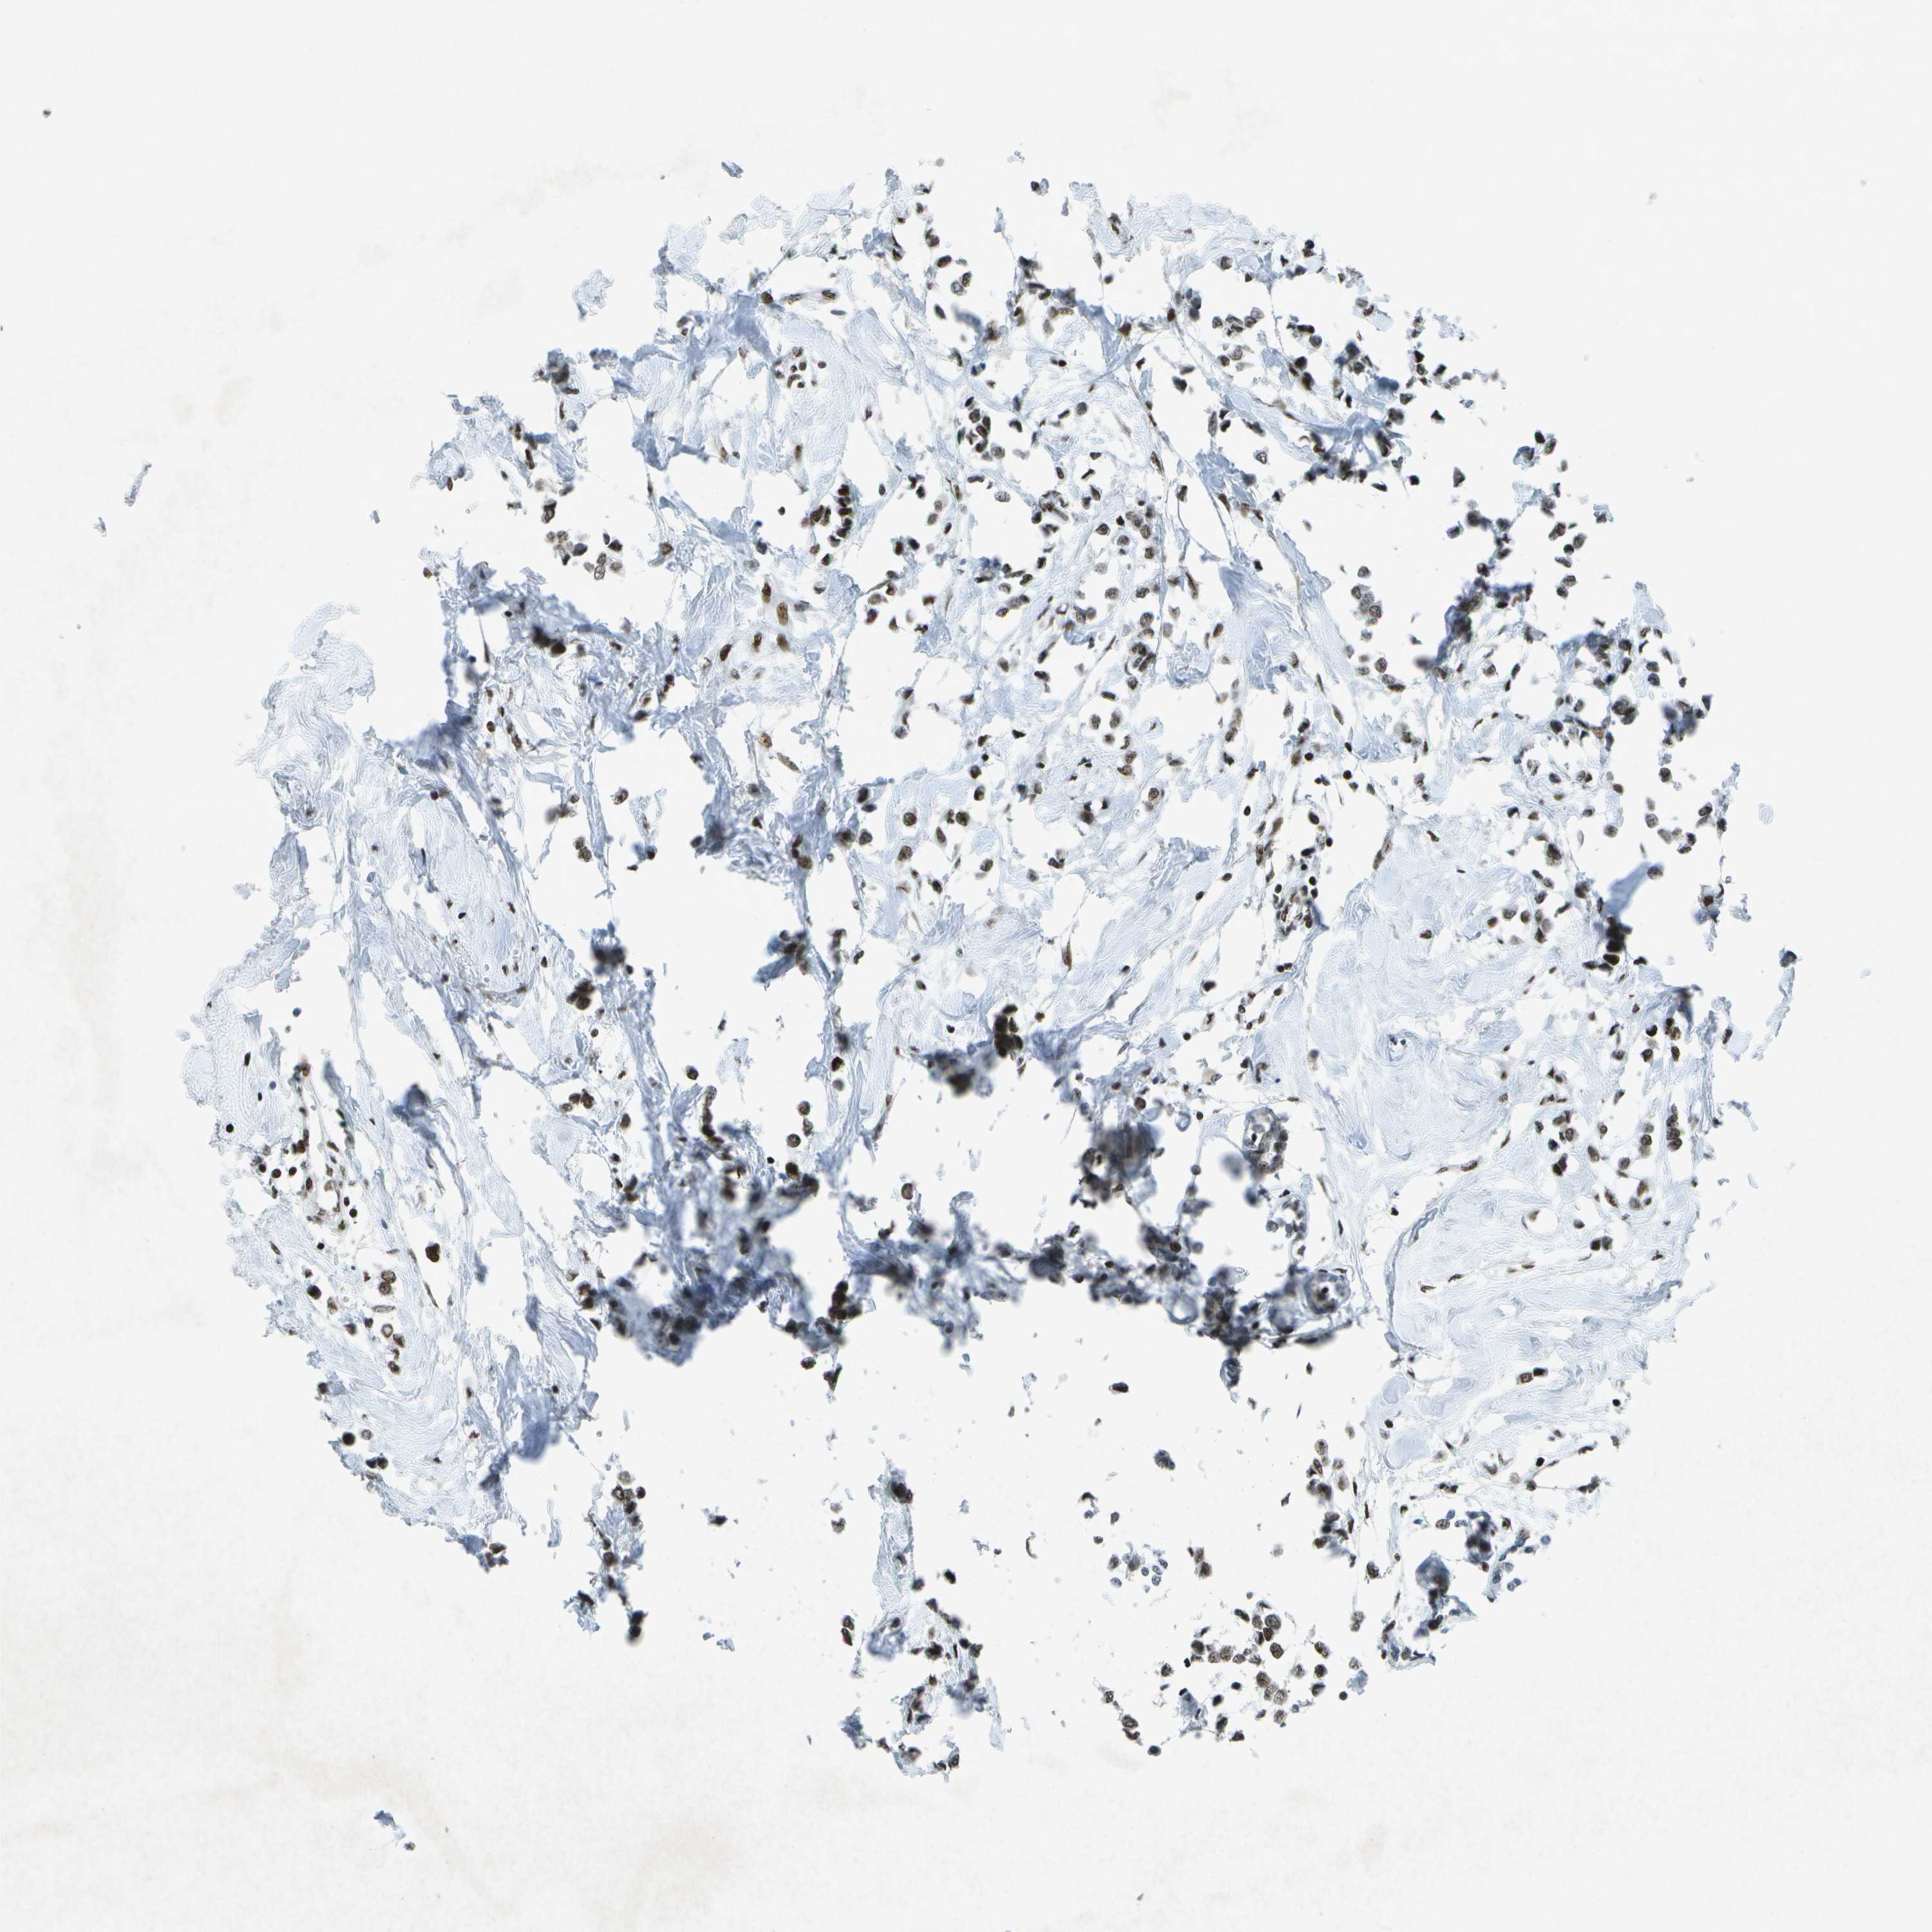

BRCA TCGA BRCA VALIDATION PROTEIN EXPRESSION

Breast cancer

Human cancer

Breast invasive carcinoma

TCGA RNA samplesi

RNA-seq data is reported as average FPKM (number Fragments Per Kilobase of exon per Million reads), generated by the The Cancer Genome Atlas (TCGA) .

Normal distribution across the dataset is visualized with box plots, shown as median and 25th and 75th percentiles. Points are displayed as outliers if they are above or below 1.5 times the interquartile range. FPKM values of the individual samples are presented next to the box plot.

Average pTPM 64.4

Number of samples 1022